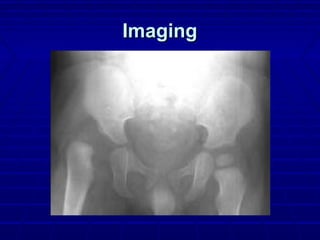

ImagingImaging

 X-raysX-rays

 Femoral head ossification centerFemoral head ossification center

 4 -7 months4 -7 months

 UltrasoundUltrasound

 Operator dependentOperator dependent

 CTCT

 MRIMRI

 ArthrogramsArthrograms

 Open vs closed reductionOpen vs closed reduction

 RadiographsRadiographs